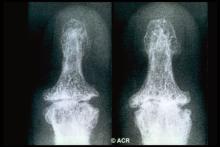

Why Would Hand OA Be Less Severe in Black People?

Osteoarthritis (OA) of the hand was less severe according to objective and pain-related markers in Black patients versus those of other racial/ethnic groups after adjustment for known risk factors, researchers found.

The finding was a major surprise and somewhat mysterious, insofar as previous studies have shown that OA of the hip and knee tended to be worse in Black people than in others. Indeed, it's unclear why race in and of itself would have any bearing on OA development.